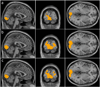

Arterial-spin-labeling (ASL) magnetic resonance imaging (MRI) provides a noninvasive tool to measure cerebral blood flow (CBF) and is increasingly used as a surrogate for baseline neural activity. However, the power of ASL MRI in detecting CBF differences between patient and control subjects is hampered by inter-subject variations in global CBF, which are associated with non-neural factors and may contribute to the noise in the across-group comparison. Here, we investigated the sensitivity of this technique and proposed a normalization strategy to better detect such a difference. A "model" situation was employed in which two visual stimuli (i.e. cross fixation and flashing checkerboard) were presented to two groups of subjects to mimic "control" and "patient" groups (N=7 for each group), respectively. It was found that absolute CBF (aCBF) in the occipital lobe in the checkerboard group was 26.0% greater compared to the fixation group, but the level of significance was modest (P=.03). In contrast, when normalizing the CBF with whole-brain CBF or CBF in a reference region [termed relative CBF (rCBF)], the statistical significance was improved considerably (P<.003). For voxel-based analysis, the rCBF indices correctly detected CBF differences in the occipital lobe in the across-group comparison, while aCBF failed to detect any significant cluster using the same statistical threshold. We also performed Monte Carlo simulation to confirm the experimental findings and found that the power improvement was most pronounced when signal-to-noise-ratio is moderate and the underlying CBF difference was small. The simulation also showed that, with the proposed normalization, a detection power of 80% can be achieved using a sample size of about 20. In summary, rCBF is a more sensitive index to detect small differences in CBF, rather than the much-sought-after aCBF, since it reduces data noise caused by inter-subject variations in global CBF.